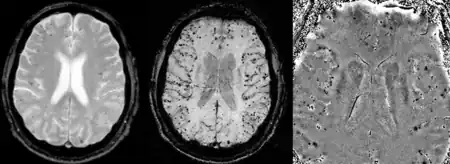

Cerebral amyloid angiopathy can be presented with lobar intracerebral hemorrhage or microbleeds in the brain. The bleeding usually occurs on the surfaces of the brain in contrast with intracranial haemorrhage due to high blood pressure which occurs in deep locations of the brain such as basal ganglia and pons. In lobar intracerebral bleed, computed tomography (CT) scan would show hyperdense haemorrhage area and hypodense odema around the haemorrhagic site.[19]

MRI sequence of gradient echo and susceptibility weighted imaging (SWI) are useful in detecting microbleeds and deposition of iron on the brain cortex (cortical superficial siderosis).[19] Other MRI indicators of CAA include white matter hyperintensities and cortical thinning.[30]